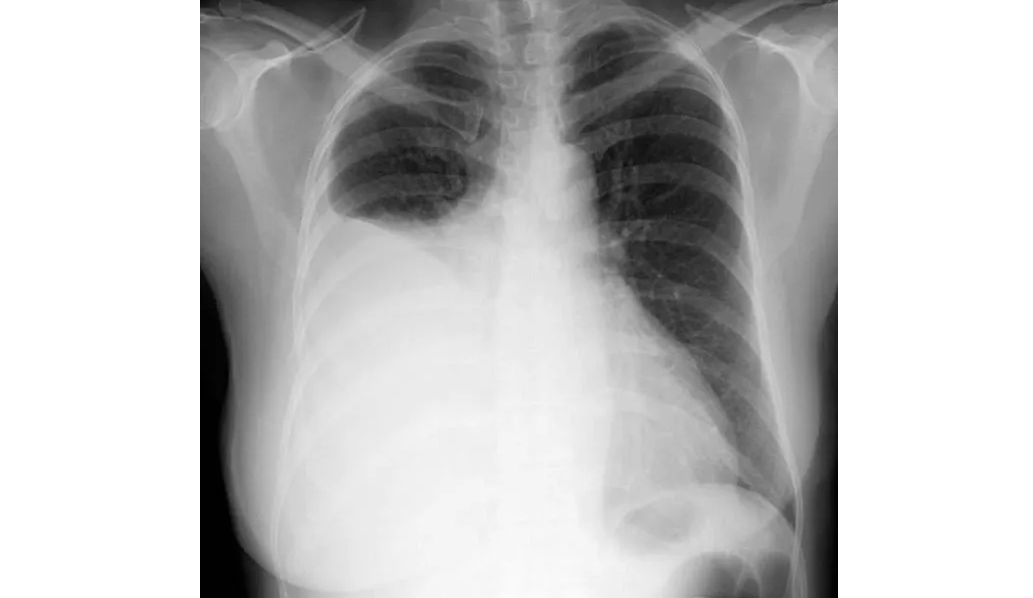

En este estudio sobre farmacocinética de antibióticos realizado en pacientes con derrames pleurales infectados se encontró que los antibióticos de uso común, como amoxicilina, metronidazol, piperacilina-tazobactam y clindamicina, alcanzan niveles en el líquido pleural equivalentes a los de la sangre y por encima de la CIM para las bacterias que se sabe que causan infección pleural. La preocupación sobre la penetración de antibióticos de uso común en el espacio pleural infectado (excepto por la trimetroprima)  son infundadas. Thorax, 4 de julio de 2024.